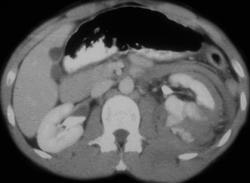

Subcapsular Hematoma